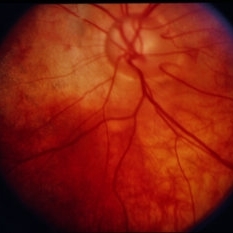

Linear Nevus Sebaceous Syndrome

Linear Nevus Sebaceous Syndrome

Feb 20 2015 by H. Michael Lambert, MD

Color photo of retina histopathology of linear sebaceous nevus syndrome.

Condition/keywords: linear nevus sebaceous syndrome

Linear Nevus Sebaceous Syndrome

Linear Nevus Sebaceous Syndrome

Feb 20 2015 by H. Michael Lambert, MD

Color photo of retina of linear sebaceous nevus syndrome.

Condition/keywords: linear nevus sebaceous syndrome